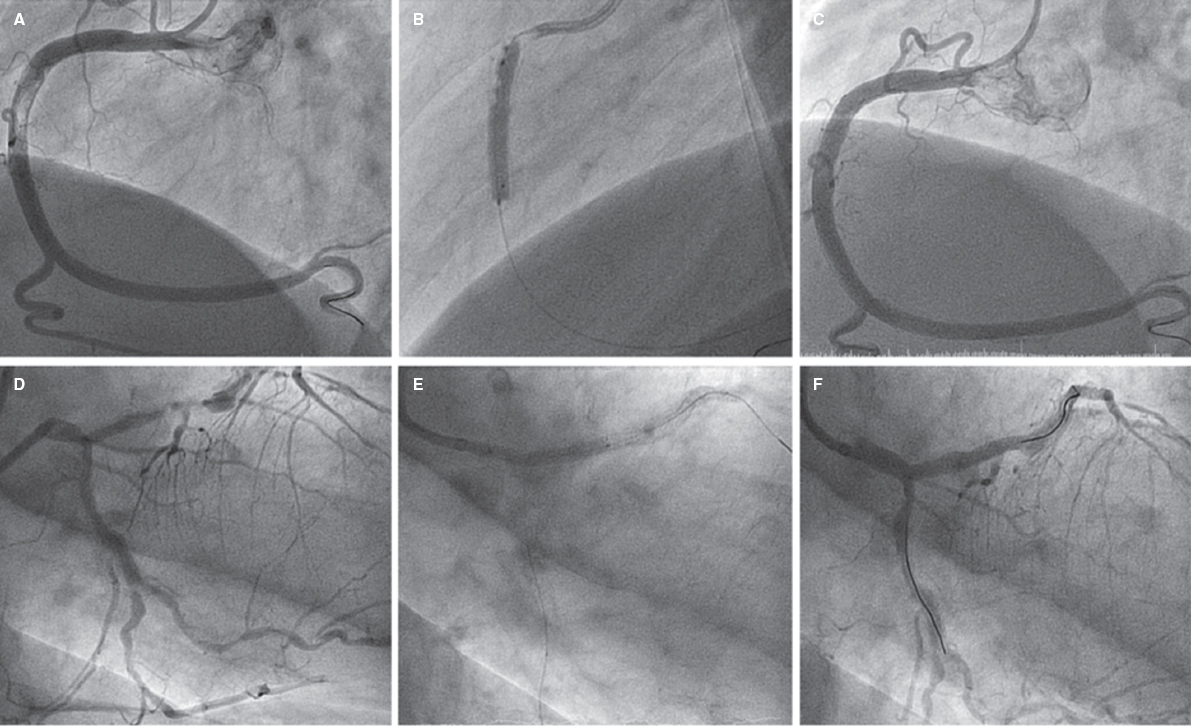

Ectasia and great proximal-distal diameter mistmatch at the lesion were the main indication for the use of this stent, in 72.6% of the lesions, with a mean vessel reference diameter of 4.1 mm ± 0.8 mm. A certain size was required to use this type of stent. The percutaneous coronary interventional on a bifurcation was the second most common indication, in 27.4% of the patients (2 of them on the LMCA). The most common type of bifurcation according to the Medina classification was 1-1-0, in 9 cases (52.9%). The secondary branch was damaged in 17% of the patients. The provisional stenting technique was the most widely used in 15 cases (88.2% of bifurcations) re-crossing to the secondary branch in 9 of them (60%). The dilatation of the secondary branch only occurred in 7 patients and only in the other 2 stents were implanted: one in a 0-1-1 bifurcation according to the Medina classification (minicrash technique) and the other in a 1-1-1 bifurcation according to this classification (TAP technique [T-and protrusion technique]). In both cases the STENTYS Xposition S stent was implanted in the main vessel and a non-self-apposing stent in the secondary branch (figure 1).

Figure 1. A: lesion with significant thrombotic load in the mid right coronary artery, which remains after thrombus aspiration. B: 3.5-4.5 mm × 27 mm Xposition S direct stent implantation. C: final angiographic result. D: significant stenosis in distal left main coronary artery. E: 3-3.5 mm × 27 mm Xposition S stent implantation from the proximal left main coronary artery to the left anterior descending coronary artery. F: angiographic result after postdilatation.